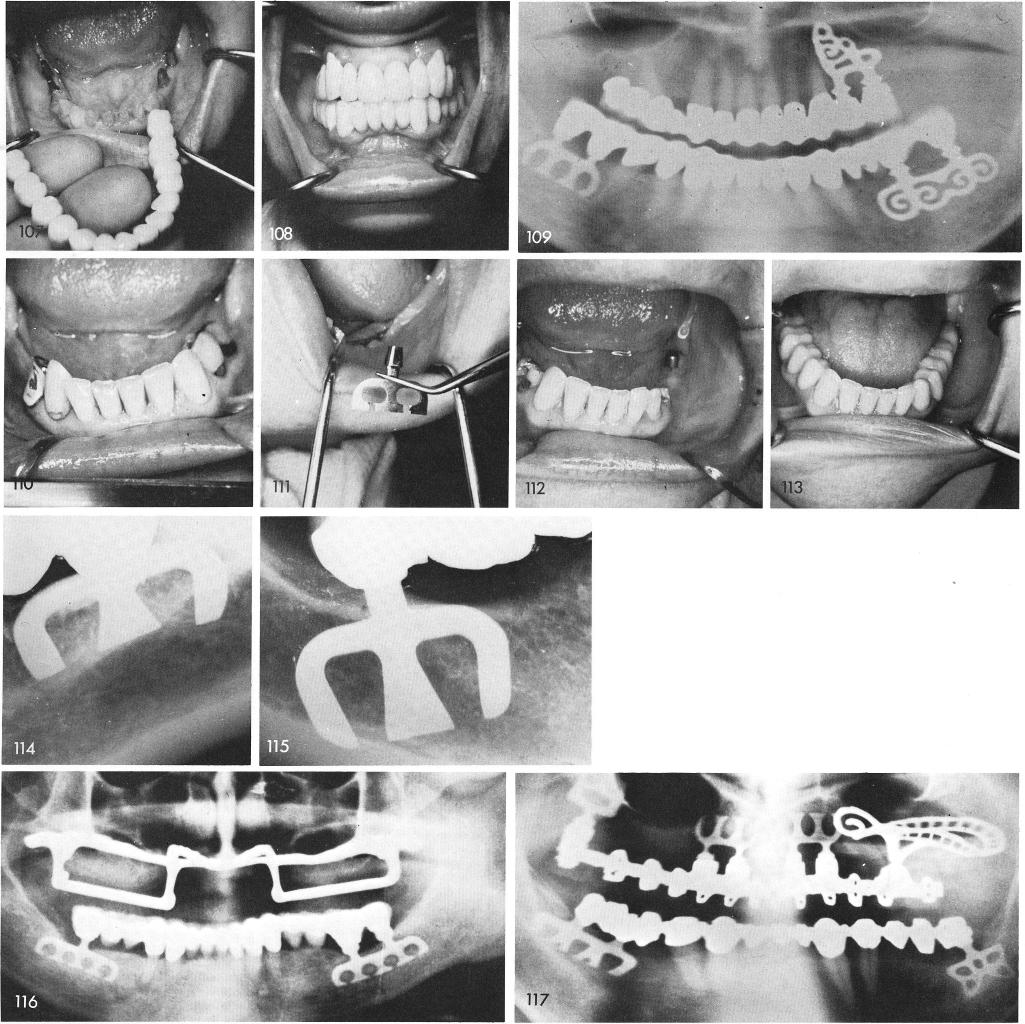

One of my earliest cases of blades is seen here, fig. 110. The early designed blades were inserted, figs. 111, 112, and the final restorations cemented into proper position, fig. 113. Periapical post-operative films show the excellent results. These were ten and one half year post-operative x-rays, figs. 114, 115. Fig 116 through 147 shows final x-rays of unilateral and bilateral posterior blades.

1 Early designed mandibular type blade implants